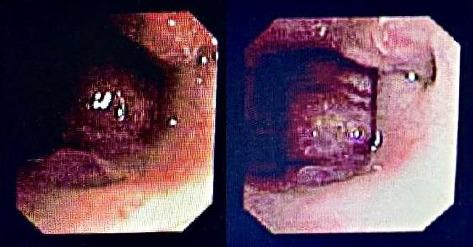

肿物测量值为24 × 25 毫米,颅底没有骨缺损,考虑血管瘤。查体见患儿口内肿物突出,排除其他部位血管瘤后行支气管镜检查显示悬雍垂全长肿块(图3)。经口入路切开软腭后发现以鼻咽区为中心的血管肿块,延伸到口咽,位于悬雍垂后(图4)。在图5中,肿块被经口取出,彻底切除肿块和悬雍垂,并烧灼止血,闭合软腭。患者继续插管5天后,第6天出现鼻腔及口腔大出血,考虑气管插管创伤引起。2天后支气管镜检查未见并发症,予以拔管。随后进行泼尼松龙治疗6个月,联合制霉菌素滴剂和普萘洛尔。患者出院并完全康复,没有出现进一步的并发症。

图3 围手术期支气管镜检查显示鼻咽梗阻性病变